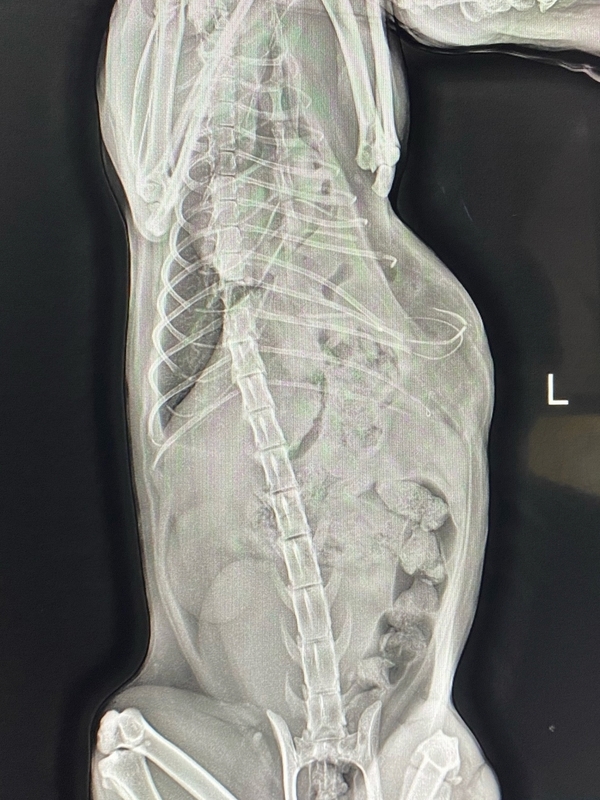

Несчастный случай, травмы и Василиса в Клинике БАРС на приеме неотложной помощи... Проведенная Rg-диагностика показала множественные переломы (один из них - открытый) и значительные внутренние повреждения со смещением органов брюшной полости в грудную клетку. Опытный ветеринарный врач, хирург [club223252442|Анна Сергеевна Кашина] знает, что в таких ситуациях медлить нельзя ни минуты, поэтому она взяла Василису на срочную операцию.

Период восстановления после травматической диафрагмальной грыжи варьируется по времени и зависит от тяжести повреждений внутренних органов, наличия кровотечения и еще ряда факторов. Травмы Василисы были очень серьезными, и, как оказалось в ходе операции, видимые переломы костей - это меньшее из зол. Прогноз был очень осторожным...